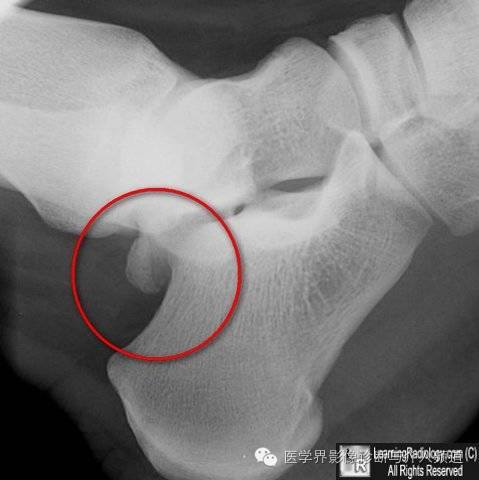

18、跟骨骨骺:为跟骨后缘骨化中心,可为多发的骨化中心。